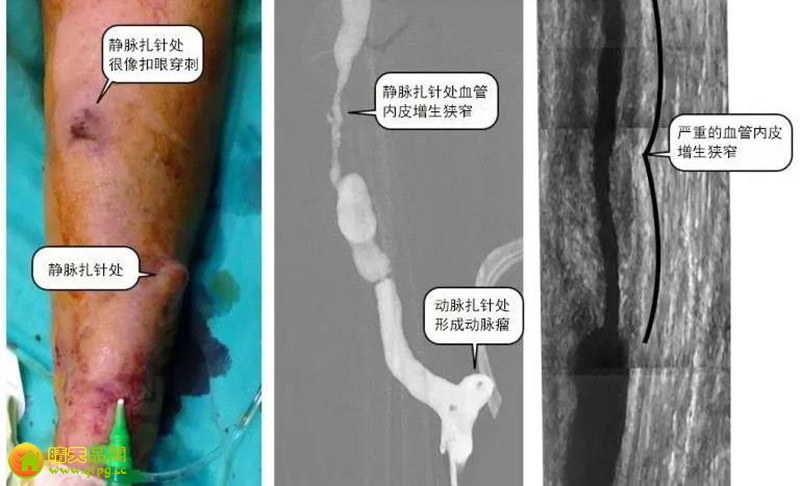

就像上图中间那张显示的,长在血管里面的“茧子”,会让内瘘狭窄,变细,最终完全堵住。你看看静脉扎针处那里,本来是多粗的血管啊,现在只有细细的一条了,保不齐哪一天就会堵住,整体内瘘都不能用了,可能又要花钱做一天新的。